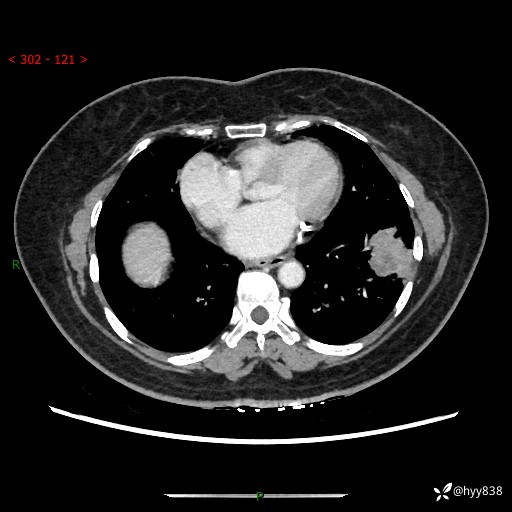

【现病史及既往史】:患者自诉2月前体检发现肺结节(左肺下叶约17mm,右肺上叶4mm),未予特殊处理,2024-10-12当地市第五医院门诊复查胸部CT提示右下肺结节(大小约3.3cm*3.9cm),患者无咳嗽、咳痰,无畏寒、发热、盗汗,无咯血,无胸闷、胸痛、呼吸困难,无恶心、呕吐,无腹痛、腹胀、腹泻等不适,现为求进一步诊治,门诊以“孤立性肺结节”收住我科。 患者本次起病来精神、食欲、睡眠尚可,大小便正常,体力、体重无明显变化。

【检查】:胸部CT增强检查